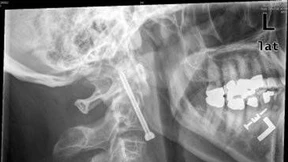

Das zunehmende Wissen um die Heilung von Knochenfrakturen und die Entwicklung von Medikamenten, die im Knochen wirken: Beides führt bei der orthopädischen Chirurgie zu neuen Forschungsansätzen.